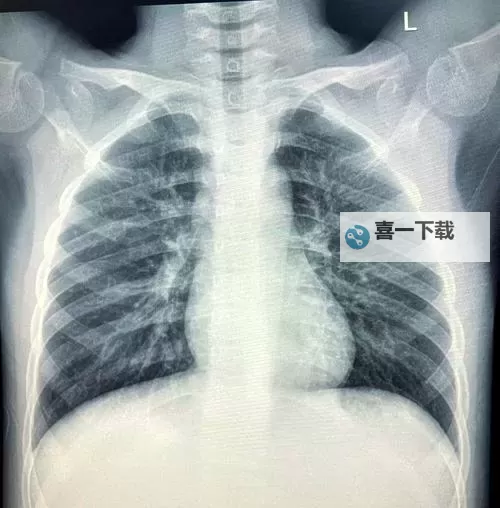

为什么会有人对胸片感兴趣?除了专业医生的临床诊断外,普通大众也希望通过了解胸片,认识常见的肺部疾病如肺炎、肺结核、肺癌等的影像表现。利用高清的胸片资料,不仅可以增强大众的医学知识,还能帮助一些初学者或医学爱好者进行学习和研究。这类资源的出现,极大地方便了人们对医学影像的获取和理解,使医学知识的普及迈出了重要一步。

另外,对于医学生或医学爱好者而言,这类“免费观看大全”不仅可以作为学习的辅助资料,也能帮助他们在临床中更好地观察和理解不同疾病的影像表现。例如,肺部感染、肿瘤、心脏或血管方面的变化,均可以通过高清胸片资料进行比对学习,从而提高诊断能力。不断丰富和更新的影像资料库,也为医学教育提供了宝贵的资源,更好地促进了医学知识的普及和专业能力的提升。